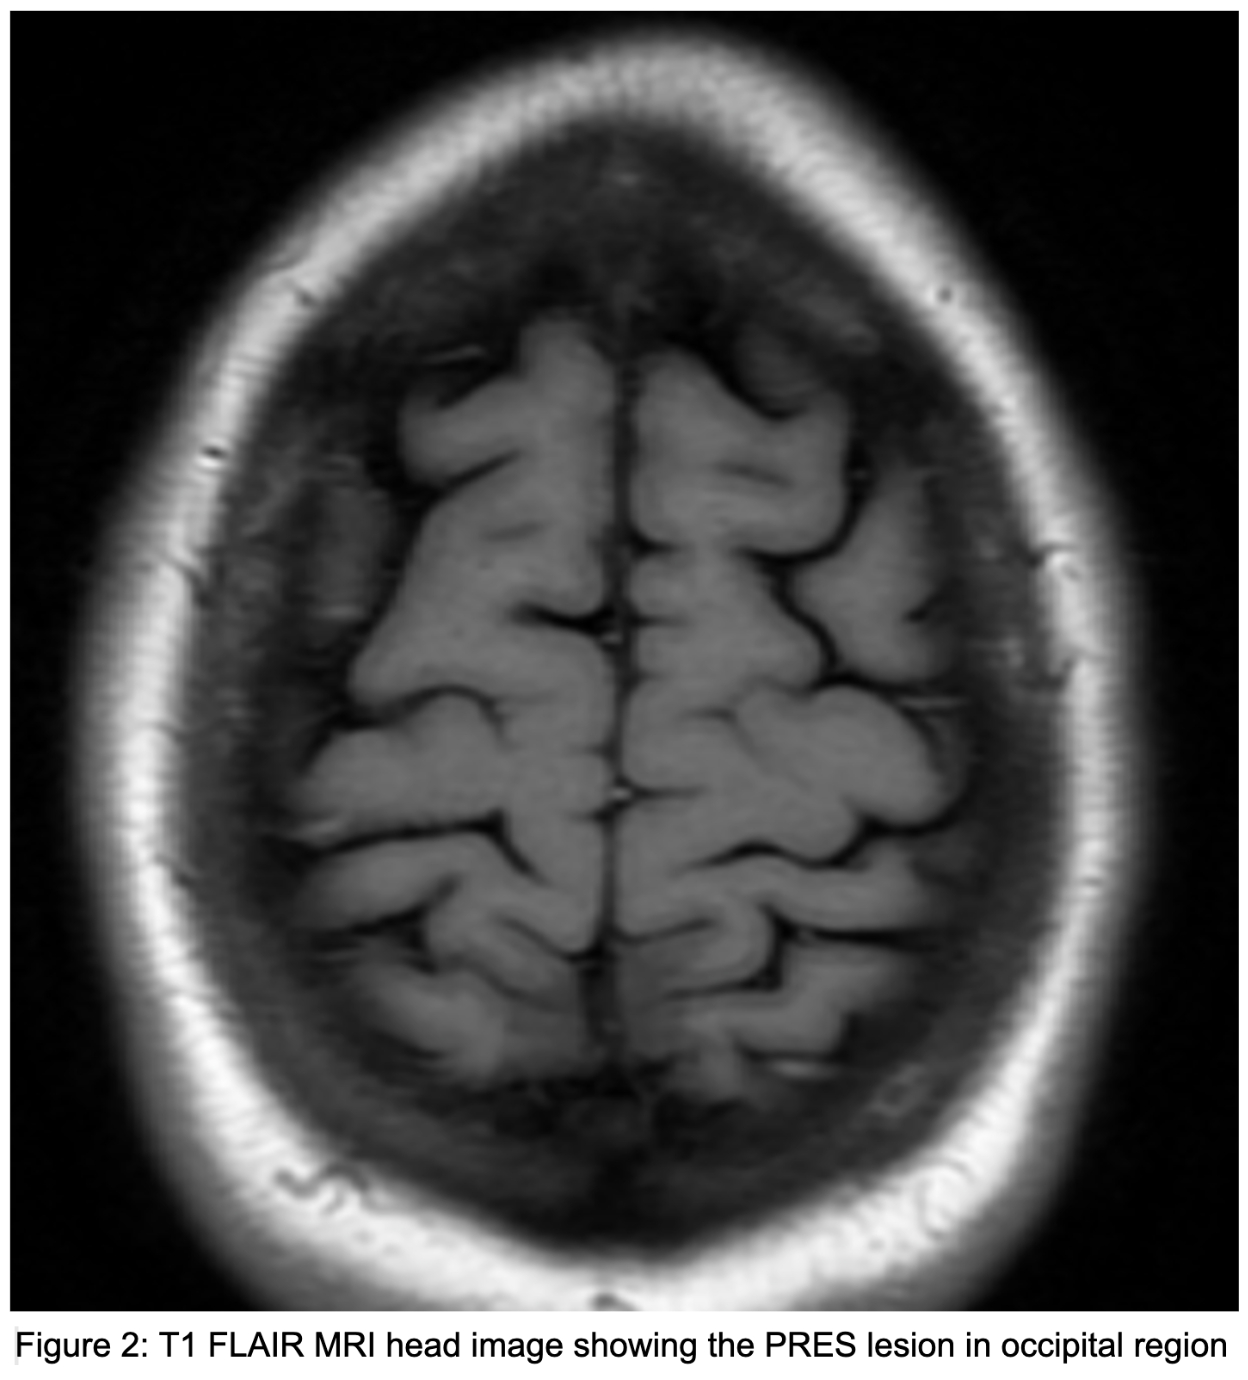

CASE PRESENTATION – A 32-year-old female with gravida 8, parity 3, abortions 4 and ectopic pregnancy 1, status post a recent normal vaginal delivery 10 days back, but with no significant past medical history, was brought to the ED after a witnessed seizure at home. She had been having a generalised headache for the past few days but could not remember details of the seizure. She complained of associated neck and back pain but denied nausea, vomiting, fever, chills, shortness of breath, chest pain, dizziness, and excessive vaginal bleeding. She had an uncomplicated vaginal delivery recently, and it was her 8th pregnancy, with the previous two being normal deliveries. The patient had seizure episodes at the hospital and mildly elevated blood pressure on admission. She was evaluated by gynaecology and was started on magnesium drip for possible eclampsia. Magnesium level was followed and maintained at 5-8 mg/dl. EEG done showed seizure potentials, but no active seizures. She got amlodipine and labetalol for elevated blood pressure. MRI brain showed subcortical white matter disease in the parieto-occipital region, with PRES. She was started on Keppra 500 mg twice daily. Her symptoms got better over a few days.

DISCUSSION – With the exact aetiology of PRES being not completely clear, one hypothesis is various risk factors causing vasospasm followed by hypoperfusion resulting in brain vasogenic edema leading to PRES. Late postpartum eclampsia with PRES is not that common. Particularly in PRES, visual impairment is common, with some patients showing decreased or asymmetric limb muscle strength, while tendon reflexes being active. The neurological symptoms, signs and radiographic changes usually disappear completely in 1-2 weeks, but if diagnosis gets delayed, then irreversible damage of neurones can occur, leading to permanent damage and also making it even life-threatening. As symptoms of pre-eclampsia does not get reported, very few get diagnosed with it at the first place, increasing the risk of onset of PRES. This particular case illustrates post vaginal delivery in females, it's important to be vigilant for maintaining normal blood pressure.